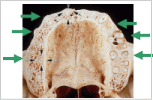

5.上顎歯列弓の舌側限界

![]() |

口蓋板 |